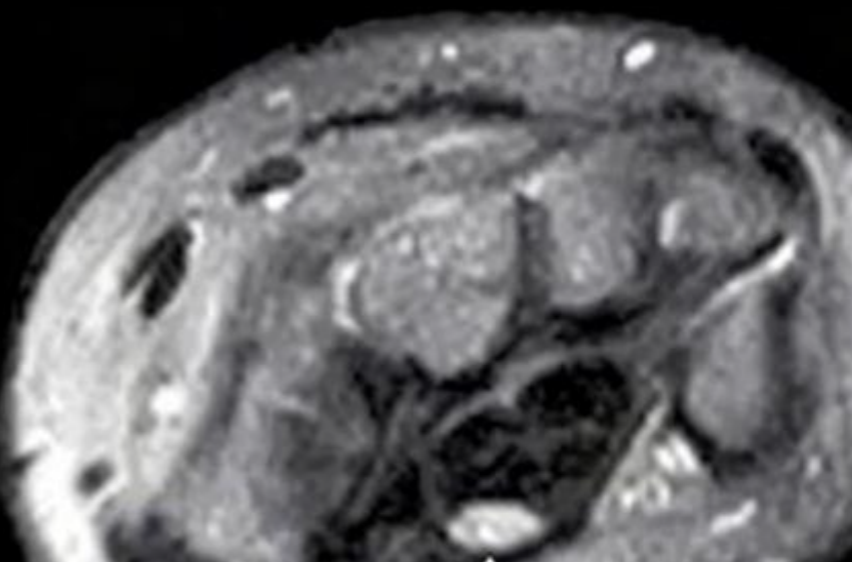

RM Tenosinovitis de quervain

Hiperintensidad T2 tendon

Edema subcutáneo peritendinoso

Captación del contraste